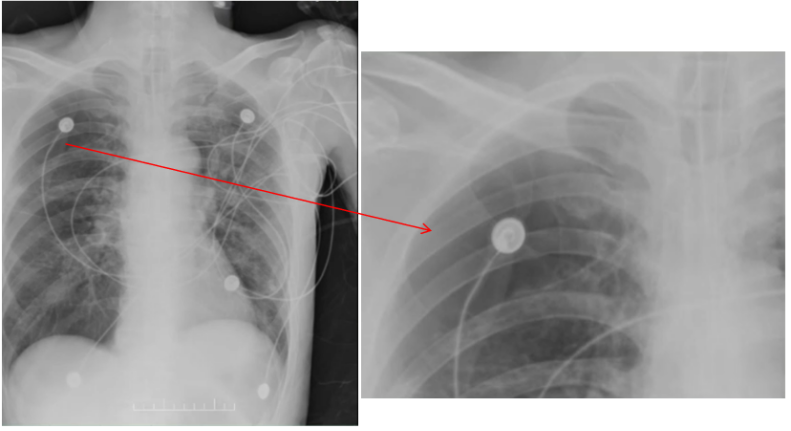

床旁胸片示:右侧弧形向内的透亮影【考虑可能是肺大疱的位置】,两肺散在模糊影,左侧少量气胸已显示不清,无明显右气侧气胸迹象(图2)。